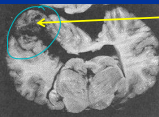

Leukoencephalomalacia: mycotoxin Moldy Corn Poisoning

Et: Fusarium verticilloides (fumonisin B1),

liquefactive necrosis of cerebral hemispheres and liver damage

Cs: rapid progressive signs, ataxia, blindness, seizures, agitation, death

Dt: toxin in feed

Tx: Euthanasia